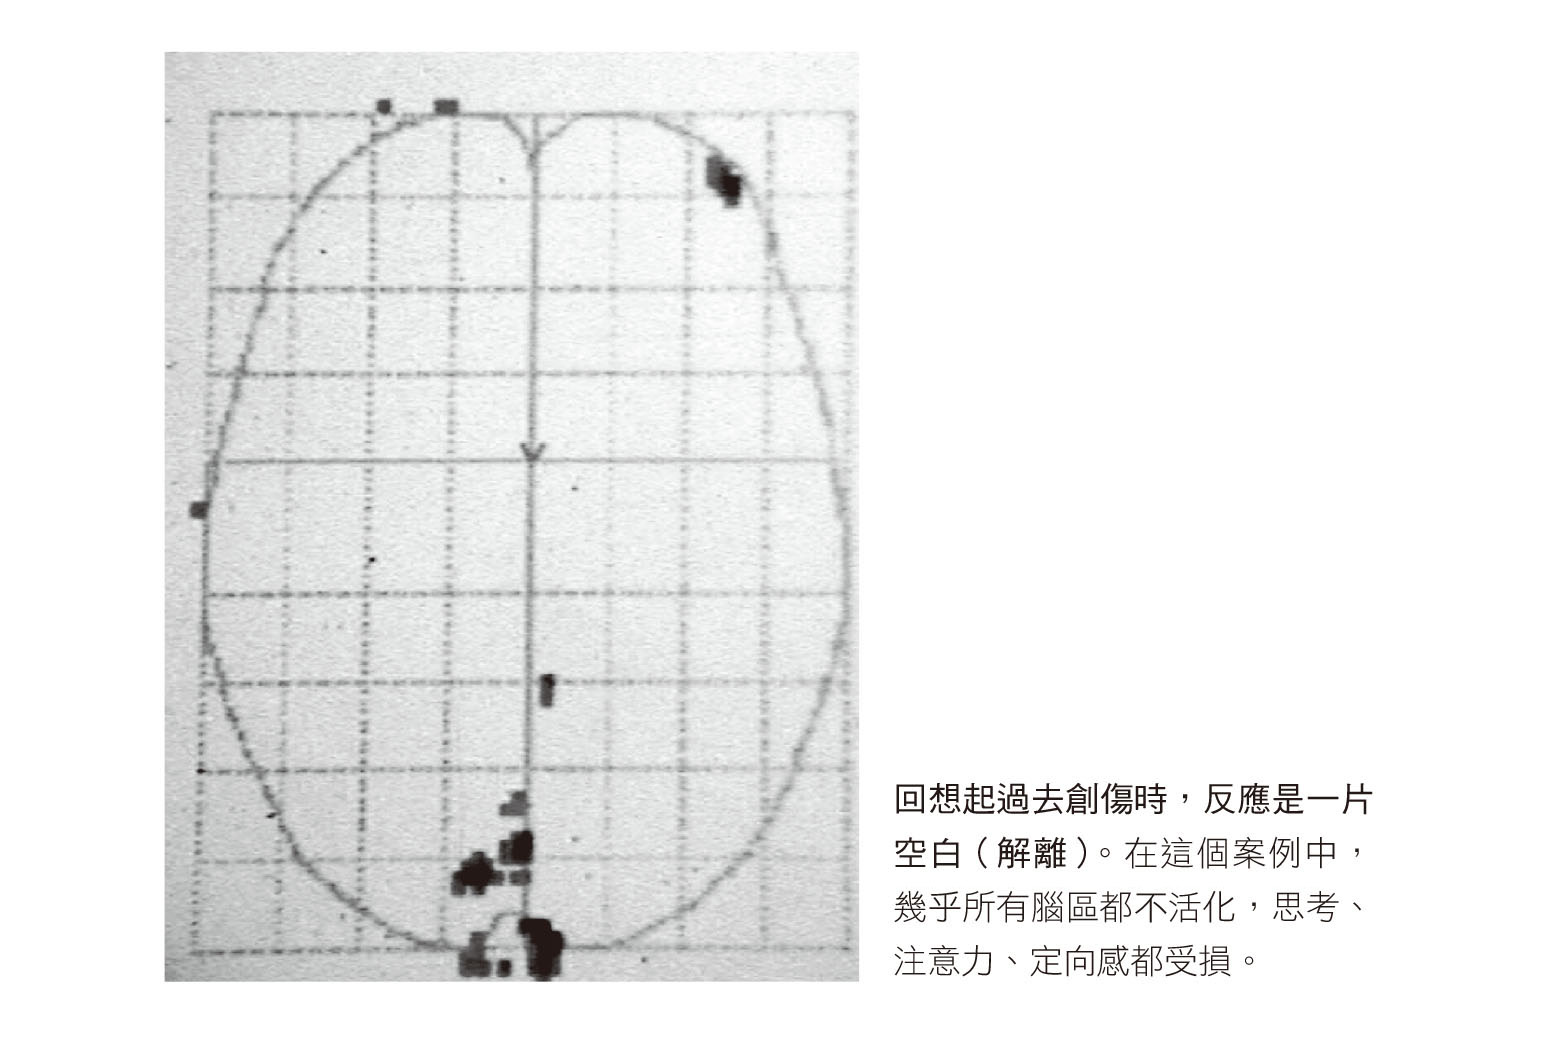

在本章結尾,我將以兩張腦部掃描來說明創傷壓力的核心特質:無止境地一再經歷,重新經驗影像、聲音和情緒,以及解離。

● 史登和烏妲的大腦

史登的腦部掃瞄顯示情境再現正在發生,腦中再次經歷創傷時就像這樣:右下方亮起,左下方暗掉,以及中心附近四個對稱的空白(你或許已經認出它與第三章哈佛研究提到的亮起的杏仁核與離線的左腦極為類似)。史登的杏仁核沒有區別過去與現在,活化的情形彷彿車禍就發生在掃瞄儀內,並激發了強烈的壓力荷爾蒙和神經系統的反應,造成他冒汗、顫抖、心跳加速、血壓升高。當一輛卡車撞上你的車子時,這些反應完全正常,且可能救你一命。

大腦前方有兩個白色區域(下圖的上方),就是左、右腦的背外側前額葉皮質,這兩區若不活化,人會失去時間感,被困在某一刻,感覺不到過去、現在與未來。16

史登的掃瞄顯示,腦部結構在原始創傷事件中受到重擊(這是該事件一開始被大腦標記為創傷的原因),惟有這些腦部結構恢復正常運作,他才能從創傷中復原。只有當一個人真正活在此時此刻,感受到最大的平靜、安全與踏實,我們才能讓他在治療中回顧過去。(「踏實」意味著你可以感覺到屁股坐在椅子上、看見光線從窗外照進來、感覺到小腿的張力、聽見風吹動屋外的樹木。)唯有穩穩固定在當下的時刻經歷創傷,才有可能深刻明白恐怖的事件已經過去。要做到這件事,大腦的瞭望臺、廚師和計時器都需要上線。若是患者不斷被拉回過去,治療就無法產生效用。

再次觀察史登情境再現時的掃瞄,會看到大腦下半部還有兩個白色空洞,這是他的左、右視丘,兩者就像在原始的創傷事件中一樣,都於情境再現時停止了運作。先前提過,視丘的功能就像「廚師」,是收集眼、耳、皮膚輸入訊息的中繼站,將感覺訊息整合成我們的自傳式記憶。視丘故障可以說明創傷記憶的形式為何不是故事(有開頭、過程與結尾),而是一些獨立的感覺印痕:影像、聲音和身體感覺,伴隨著強烈的情緒,通常是恐懼與無助。17

現在看烏妲在掃瞄儀內的經驗。每個人對於創傷的反應都不盡相同,但從烏妲身上可以看到特別戲劇化的差異。車子被撞時,她就坐在史登旁邊,但她對創傷腳本的反應是完全麻木:腦中一片空白,幾乎所有腦區都顯示出活動明顯減低,心跳與血壓亦無升高。當她被問及掃瞄過程中的感覺時,她說:「就跟車禍時一樣:毫無感覺。」